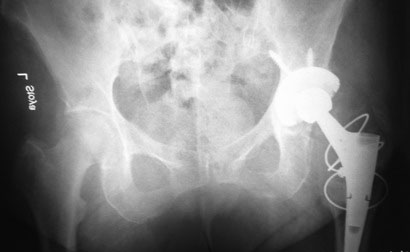

На консультации женщина 64 лет.

Беспокоят ноющие боли по по передней поверхности правого тазобедренного сустава около года. В течение последнего месяца боли усилились, вынуждена пользоваться костылями. Оперирована пять лет назад в Испании. Документов нет. Послеоперационный рубец, анализы, КТ – без патологии.

Вопрос: что это за протез и нормально – ли наличие такого «сочленения» в бедренном компоненте или это нарушение стабильности фиксатора?